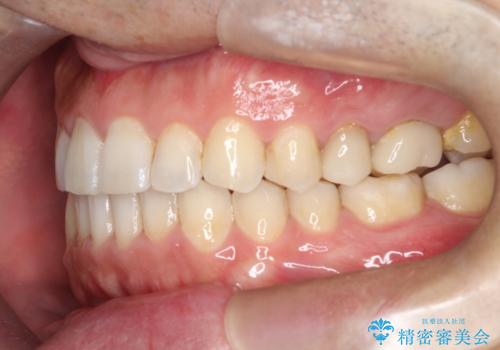

【インビザライン】前歯の隙間を閉じたい

- 前歯の隙間を主訴に来院されました。

マウスピース矯正にて、隙間を綺麗に閉じることができ満足していただきました。

前歯の隙間を閉じる際は、前歯部の突き上げが懸念されるため、適切な治療計画が必要となります。